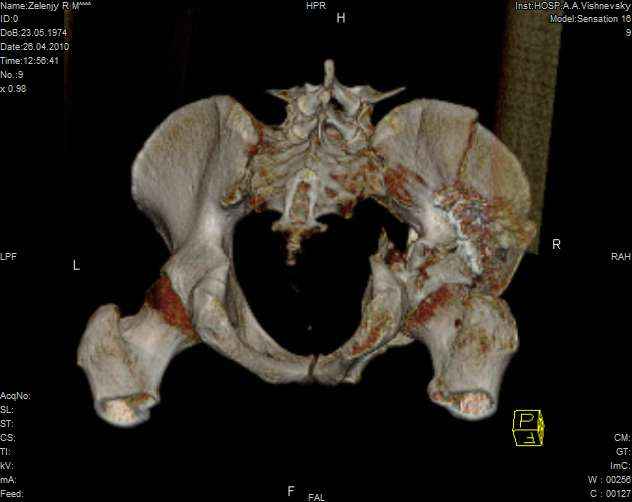

Молодой человек, 35 лет в первых числах января 2010года попал в ДТП, получил перелом правой половины таза.

Был доставлен в одну из ведущих клиник Москвы и прооперирован: была вополнена открытая репозиция и остеосинтез крыла правой подвздошной кости с прилегающей к нему края вертлужной впадины. Но по каким то, мне е понятным соображениям, перелом седалищной кости, проходищая через вертлужную впадину не был отрепонирован ( со слов пациента, доктор сказал что перелом и так срастется).

В настоящее время имеем то что имеем - видно на картинках. Пациент кода то лечился у меня, потому попросил проконсультировать его в создавшейся ситуации.

Мое мнение: пациенту конечно, рано или поздно, предстоит эндопротезирование правого тазобедреного сустава. Но хотелось бы вертлужный компонент поставить в более сформированню вертлужную впадину, чем сейчас имеется.